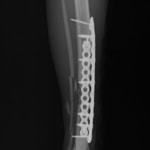

症例3:キルシュナーワイヤーのピンニングによる整復

ペルシャ猫 11ヶ月齢 雄

他院にて左大腿骨遠位の成長板骨折(salter-harrisⅠ型)が認められており、治療相談を目的として来院。当院にて、キルシュナーワイヤーを用いたピンニングにより骨折部位の整復を行いました。術後の経過は良好で、現在も経過観察中です。

術前レントゲン

術後レントゲン

機器

Arthrex社のターゲティングデバイスを用いてピンニングの位置を調整することで、確実な固定を行っています。当院ではこの手術器具以外にも、人の手術にも使用される様々な器具を導入し、手術精度を高め、また医療メーカーと新しい器具の開発、試作にも取り組んでおります。